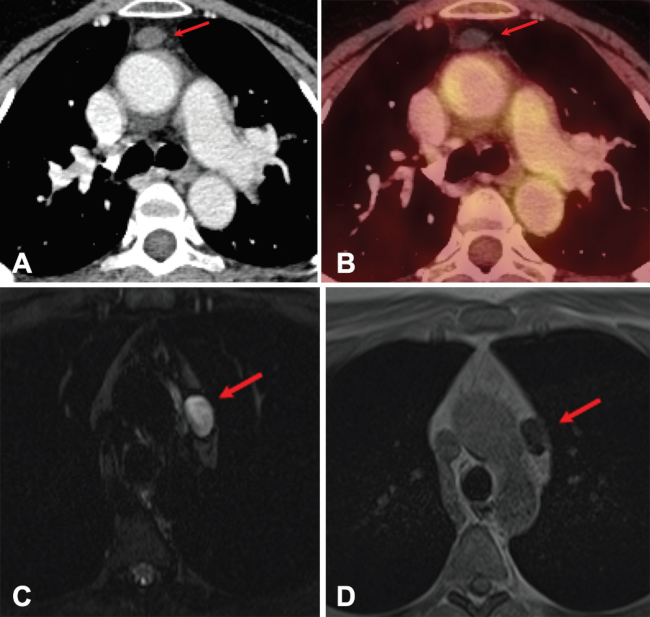

El carcinoma tímico puede ser difícil de distinguir mediante imágenes de un timoma localmente avanzado, pero el carcinoma tímico tiende a ser más agresivo, con rápida invasión de estructuras adyacentes. El carcinoma tímico por lo general carece de cápsula y las adenopatías y metástasis a distancia orientan a ese diagnóstico. Generalmente, se presentan en TC como masas multilobuladas, heterogéneas con áreas de necrosis y calcificación. Su captación es alta, típicamente con un SUVmáx mayor a 7 (►Fig. 6).6